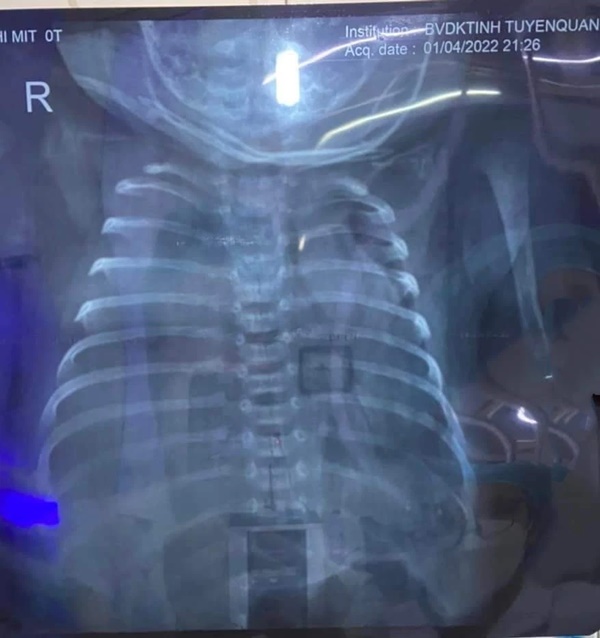

Phim chụp phổi của bệnh nhi. Ảnh: BVCC

Bệnh nhi được đưa vào Khu điều trị bệnh nhân COVID-19 điều trị tích cực. Đến ngày 1/4, siêu âm phổi có dịch, bệnh nhi xét nghiệm âm tính COVID-19 nên chuyển Khoa Nhi tiếp tục điều trị.

Tại Khoa Nhi, các bác sĩ đã chọc hút dịch màng phổi và hút ra được hơn 100ml dịch nâu sánh. Bệnh nhi được điều trị và chăm sóc tích cực, tình trạng dần ổn định hơn. Sau đó, được chuyển tuyến về Bệnh viện Nhi Trung ương để tiếp tục điều trị và theo dõi.